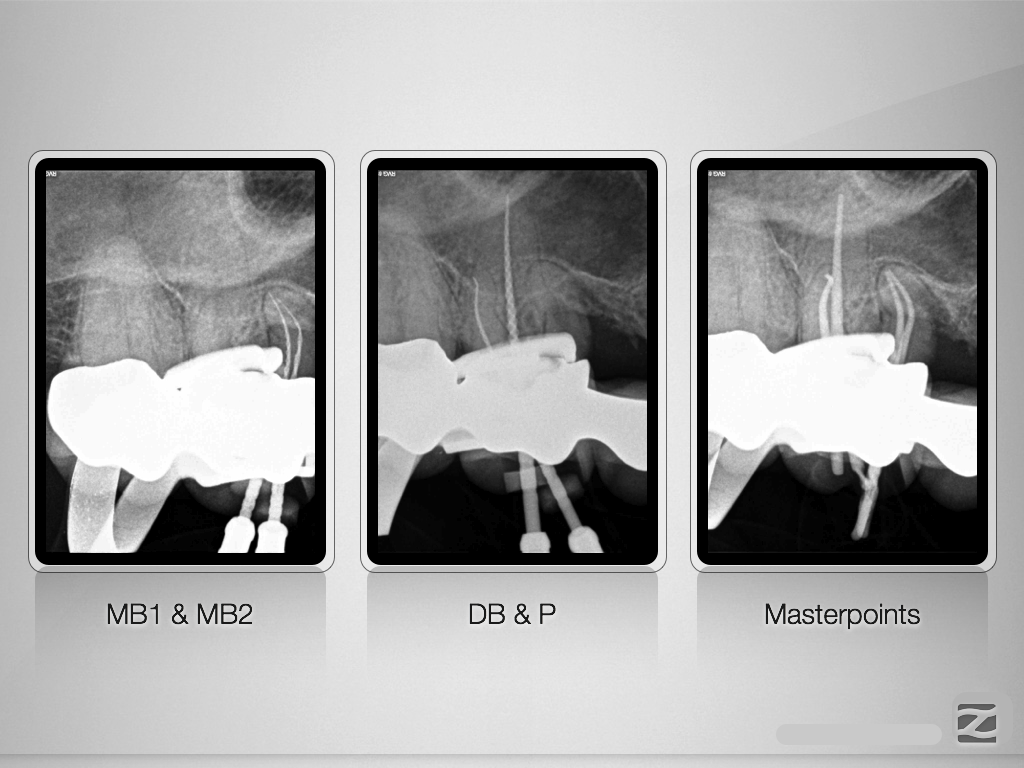

16D.006

Perforation und Krümmung